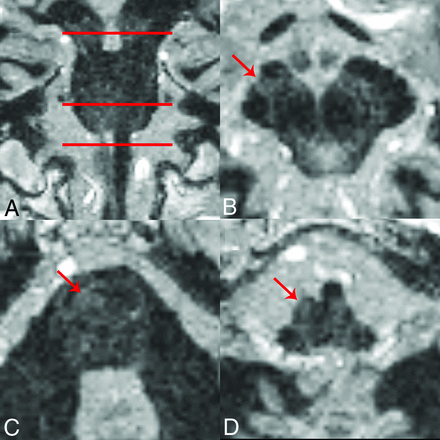

To demonstrate clinical feasibility, we used the 1-average, 1-mm isotropic FGATIR (theoretically increasing available intravoxel signal by ∼95%) to obtain images in a consented patient with prior right-sided infarct (Fig 6). Here we observed loss of the normal right corticospinal tract signal intensity in the cerebral peduncle and basis pontis, with complete absence of the right medullary pyramid. These findings were spatially remote from the site of ischemic stroke (right basal ganglia and internal capsule) and consistent with trans-synaptic degeneration of the tract.

Example of the 1-mm isotropic resolution FGATIR sequence obtained in a 53-year-old woman with a remote prior right middle cerebral artery infarct involving the posterior frontoinsular cortex and subjacent basal ganglia (not shown). A, The axial planes for B–D. There is asymmetric absence of the compact dark corticospinal tract (red arrows) in the middle third of the right cerebral peduncle of the midbrain (B), right central basis pontis (C), and right medullary pyramid (D). These images appear very similar to myelin-stained histology changes of the brain stem after chronic right-sided infarct published in a popular neuroanatomy atlas.48 This clinical example illustrates the feasibility of detecting brain stem pathology in patients using the faster, but lower 1-mm isotropic spatial resolution.